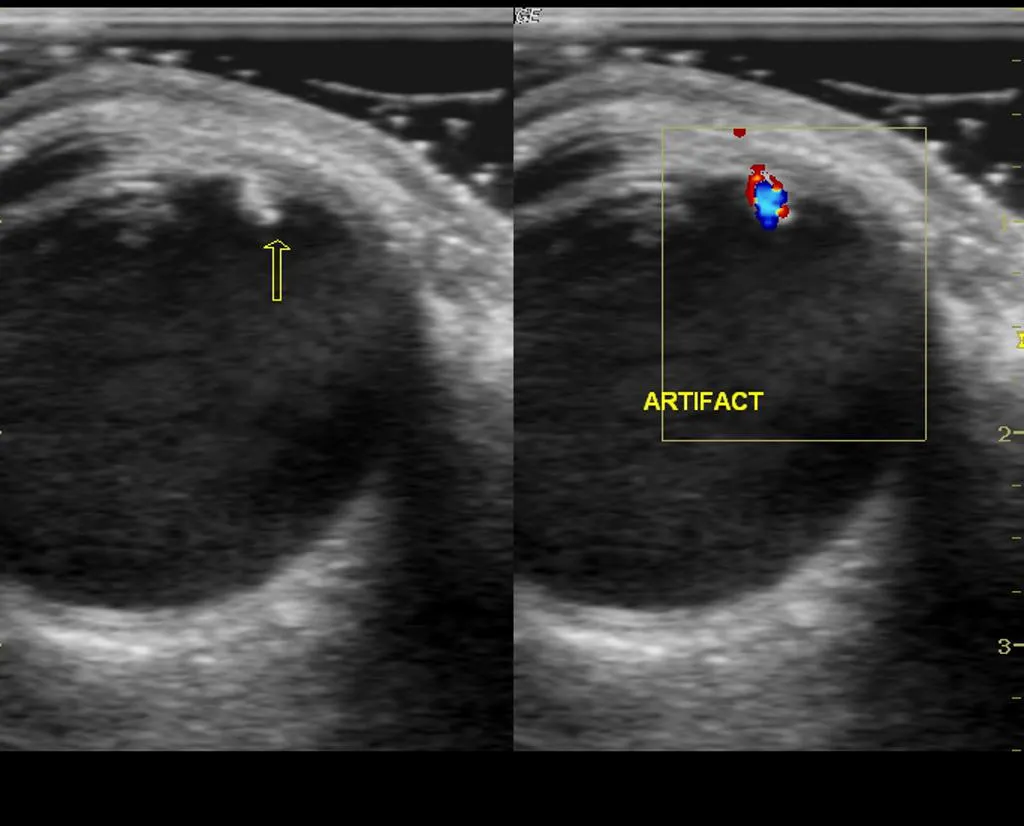

Findings:

Hyperechoic object, possibly producing shadow or comet tail artifact

Can also see “twinkle” artifact when color doppler is applied

Foreign Body – Source: Dr Maulik S Patel, https://radiopaedia.org/From the case https://radiopaedia.org/cases/21698